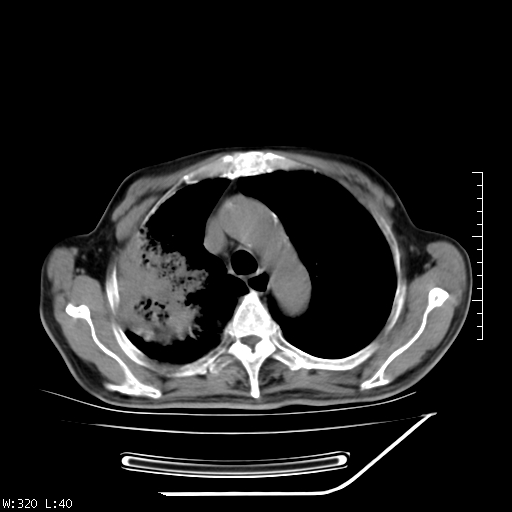

标题: CT23994:男、72、咳嗽、气短两月余,近来消瘦。 [打印本页]

标题: CT23994:男、72、咳嗽、气短两月余,近来消瘦。

右上肺实变,与胸膜关系密切,右肺容积缩小,隆突下淋巴结增大,考虑1 肺结核 2 肺癌

右上肺大片状密度增高影,与胸膜关系密切,内见低密度透亮影,胸膜下可见三角形不张影,左下肺沿支气管走形结节影,纵膈内淋巴结显示。考虑结核并疤痕性不张可能性大,建议穿刺活检,排除肺泡癌。